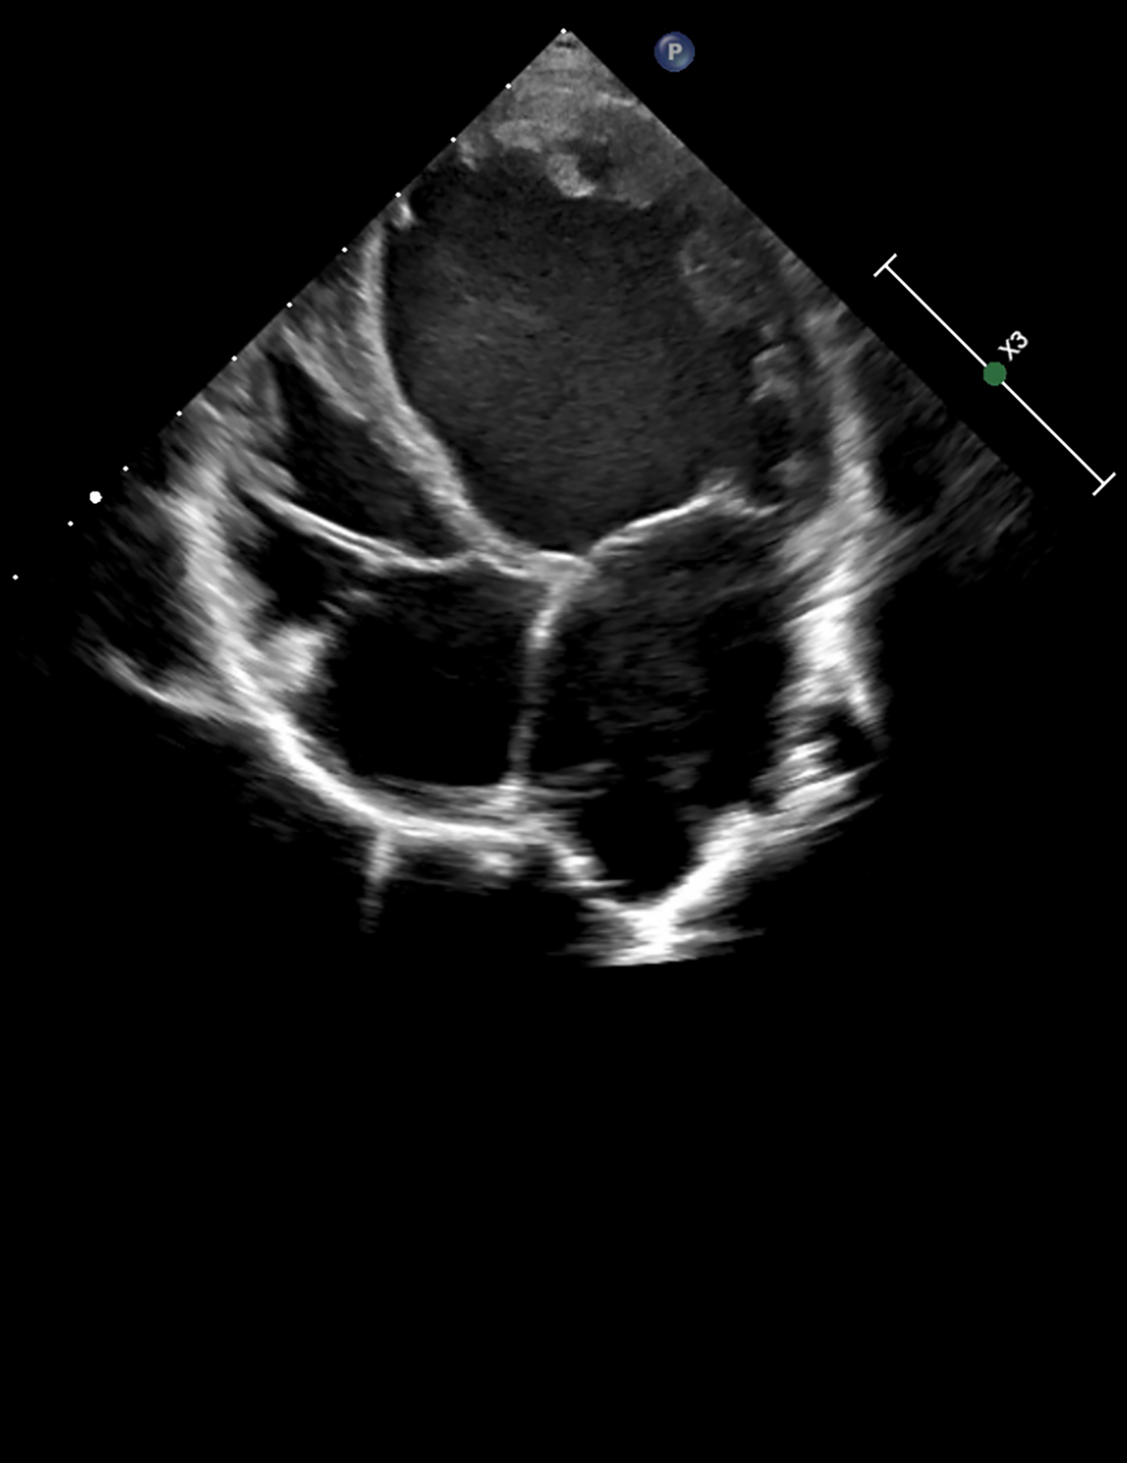

At the age of 7, the boy was admitted to a cardiac center due to a sudden deterioration in his condition. On admission, the patient's weight was 17.4 kg and he was 115 cm tall (both values were <3 percentile). There was tachycardia (approximately 160 bpm), profuse vomiting, and a quiet systolic murmur on the left side of the sternum. Blood tests showed elevated NT-proBNP (10,064 pg/ml; normal <83 pg/ml) and troponin T (86 pg/ml; normal <14 pg/ml). Chest X-ray revealed an increased cardiac silhouette (Figure 1). An echocardiogram revealed a dilated left ventricle (LVDd: 4.73 cm – Z-score: 2.7; LVDs: 4.33 cm – Z-score: 5.22) with features of non-compaction, PFO, and small regurgitations on the mitral and tricuspid valves (Figure 2). The LVEF was about 18%. The electrocardiograms (ECG) showed non-specific intraventricular conduction abnormalities, ST-T segment inversion in the V5, V6 leads and a borderline corrected QT interval (QTc) of up to 453 ms (normal: <440 ms). The Holter ECG showed ten ventricular extrasystoles. Due to the patient's deteriorating condition, a left ventricular assist device (LVAD) was implanted as a bridge to orthotopic heart transplant (OHT).

Figure 2. Echocardiographic image in a parasternal long-axis view showing the left ventricle, left atrium, and aortic root. Cardiac structures appear with clear wall delineation, suggesting preserved image quality for structural assessment.